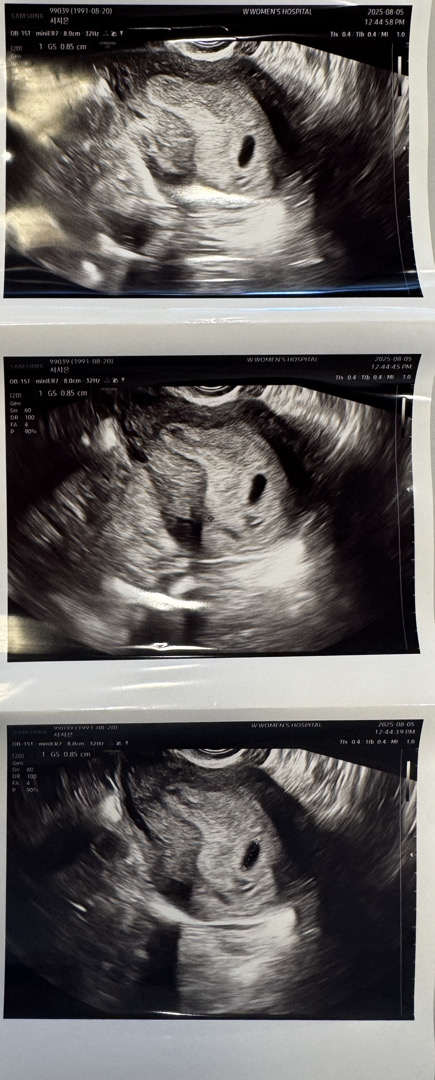

6주차 초음파

어제 막생기준으로 6주2일 (생리29일주기) 초음파로 아기집 확인하였고 초음파 볼때 난황도 보인다고 하셨는데 주신 초음파 사진에는 보이지 않아서요.. 이런경우도 있나요??ㅜㅜ 지금 배는 묵직하게 아픈 느낌있고 출혈은 없는데 이런경우 있으신분 잇나요?? 2주뒤에 병원 오라고 하셨는데 다음주에 서브병원으로 가면 심장 소리 들을 수 있겠죠..?